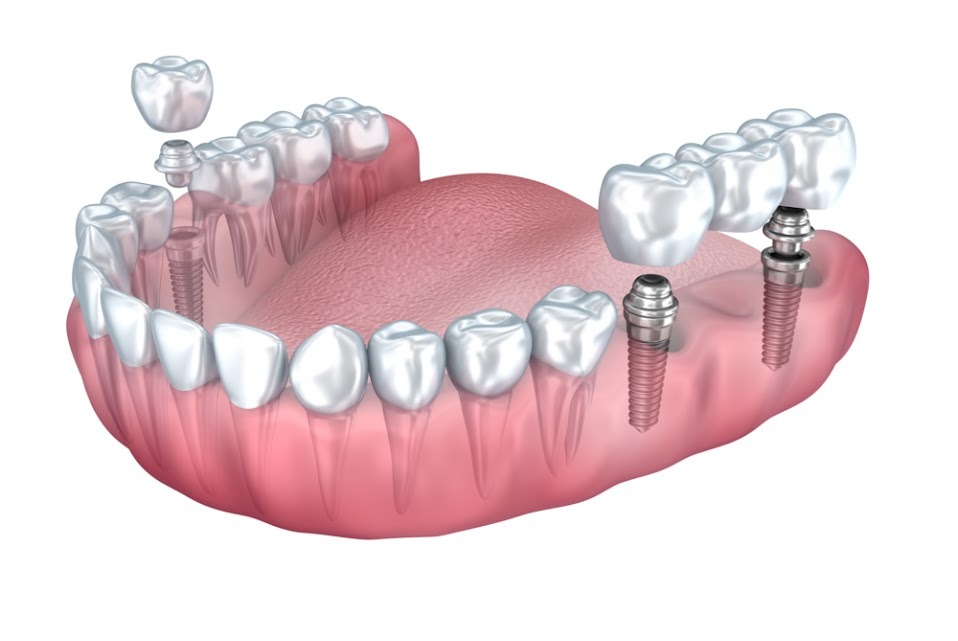

Dental Implant Placement

For patients missing multiple teeth, dental implants provide a stable and permanent solution. Our precise implant placement procedure ensures:

- Improved chewing ability and speech clarity.

- Enhanced confidence with a natural-looking smile.

- Better oral health by preventing bone deterioration.